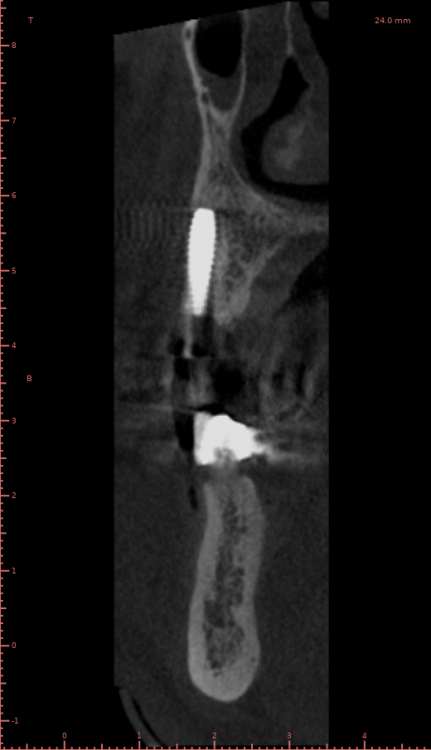

Женька Опубликовано 19 апреля, 2021 Автор Поделиться Опубликовано 19 апреля, 2021 Rg Ссылка на комментарий

Женька Опубликовано 21 июля, 2021 Автор Поделиться Опубликовано 21 июля, 2021 3 месяца минуло... клык на торке 30 неприятные ощущения второй премоляр на 10 и подвижность... отправил на кт. Всё насмарку... Ссылка на комментарий

Женька Опубликовано 2 августа, 2021 Автор Поделиться Опубликовано 2 августа, 2021 2.5 с тупым перкуторным звуком И вишенка, нет АРБУЗИЩЕ, на торте 2.3 в соседней теме в ортопедии посоветовали перестать уничтожать людям зубы, тоже самое помоему можно сказать и по хирургии... Правильно же понимаю, что протезировать такой (2.3) не стоит. Даже если торк выдержит в 35 чревато проблемами после установки постоянной ортопедии. Ссылка на комментарий